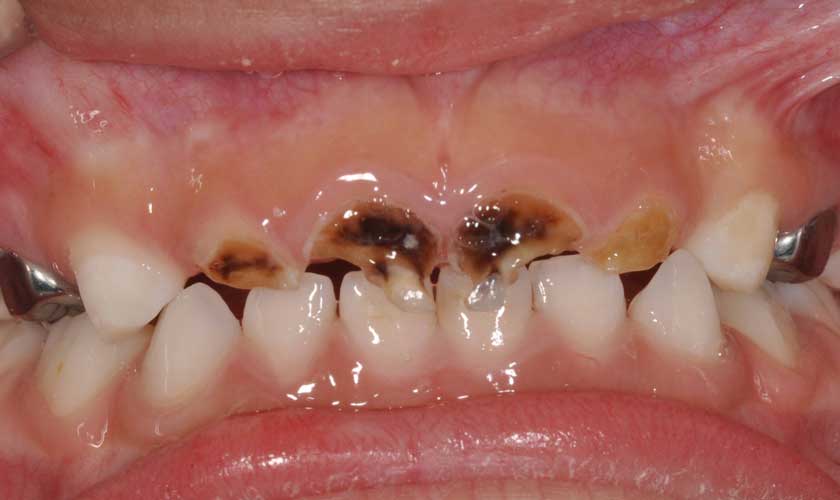

Sâu răng dưới nướu hay sâu chân răng là tình trạng sâu răng thường gặp, nếu không được điều trị kịp thời thì nguy cơ nhổ răng sẽ rất cao.

Phần lớn nguyên nhân gây sâu răng là do các chủng vi khuẩn gây sâu răng tấn công. Thông thường, vi khuẩn sẽ tấn công bề mặt nhai, phá hủy cấu trúc của răng khiến răng xuất hiện các lỗ hổng.

Theo thời gian, vi khuẩn sẽ ăn mòn thân răng và tiếp tục tấn công phần chân răng bên dưới gây ra hiện tượng sâu chân răng.

Tình trạng sâu chân răng (sâu răng dưới nướu) không chỉ gây mất thẩm mỹ, gây nên những cơn đau nhức răng mà còn có thể dẫn đến hậu quả mất răng nếu không điều trị. Do đó, việc thăm khám càng sớm càng tốt khi có dấu hiệu sâu răng là cách cần thiết để chúng ta bảo tồn răng thật của mình.